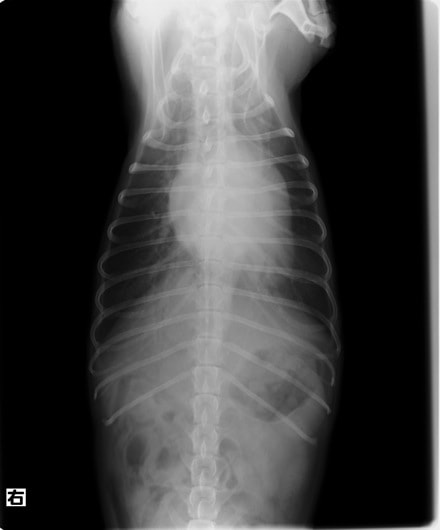

D:胸部レントゲン写真 正面像

左側胸壁心尖部領域を最強点とするLevine 5/6の収縮期性心雑音が聴取された。

胸部レントゲン検査において重度の心拡大と肺水腫が認められた。超音波検査では、重度の僧帽弁閉鎖不全症、三尖弁閉鎖不全症、中程度の大動脈弁閉鎖不全症を合併していることが判明した。三尖弁逆流速度から肺高血圧症が示唆された。

ACE阻害薬、ピモベンダン、硝酸イソソルビド徐放剤、ベラプロストナトリウム、利尿剤としてフロセミドとスピロノラクトンを用いて治療を行った。